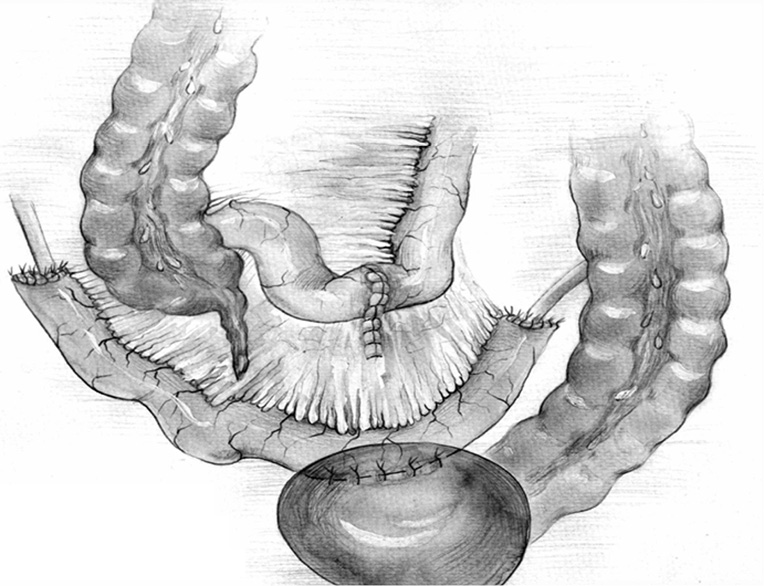

Fig. 6. The final type of ureteroileoureteroanastomosis operation with two reconfigured intestinal transplants according to Yang–Monti in our modification

Fig. 7. Multisection computed tomography contrasts with the patient 2 years after right-sided ileoureteroplasty with two intestinal transplants according to Yang–Monti in our modification

Bilateral small intestinal reconstruction of the ureters was performed in 40 (20.7%) patients. Most often, in 24 (60.0%) patients, U-shaped ileoureteroplasty was performed (Figs. 8 and 9), and more complex reconstructions were performed less often; that is, Y-shaped in 1 (2.5%) case, J-shaped in 3 (7.5%), L- and 7-shaped (Figs. 10 and 11) ileoureteroplasty in 6 (15.0%), and that with two separate ileografts in 6 (15.0%) cases.

Fig. 8. Bilateral U-shaped ileoureteroplasty